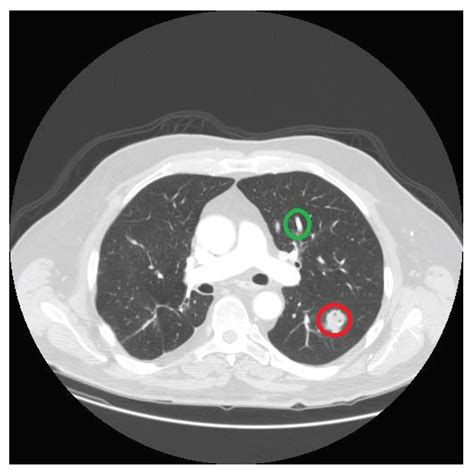

A Node In Lung Ct Scan is defined as a growth or spot measuring less than 3 centimeters in diameter. If the spot is larger than 3 centimeters, it is typically referred to as a lung mass. These structures are relatively common, often appearing as incidental findings on CT scans performed for unrelated reasons, such as a checkup after a minor injury or during a cardiac evaluation. Because these nodules are small, they are frequently invisible on standard chest X-rays, making high-resolution CT scans the gold standard for detection and monitoring.

Most nodules are the result of past exposure to environmental factors or previous infections that have healed, leaving behind a small patch of scar tissue. Other common causes include granulomas—small areas of inflammation often caused by fungal infections—or benign tumors. Because the lung acts as a filter for the body, it is a frequent site for these harmless deposits to accumulate over time.

Characteristics Analyzed by Radiologists

When a radiologist reviews a Node In Lung Ct Scan, they look for specific physical characteristics to determine the likelihood of the nodule being benign or requiring further investigation. By evaluating the size, shape, and internal density of the spot, doctors can categorize the risk level. The following table illustrates how different features are generally interpreted during a clinical assessment:

Characteristic Favorable (Low Risk) Concerning (High Risk)

Size Small (< 8mm) Large (> 8mm)

Margins Smooth, sharp borders Irregular, "spiculated" borders

Calcification Central, popcorn, or dense Stippled or absent

Growth Rate Stable over years Rapid doubling time